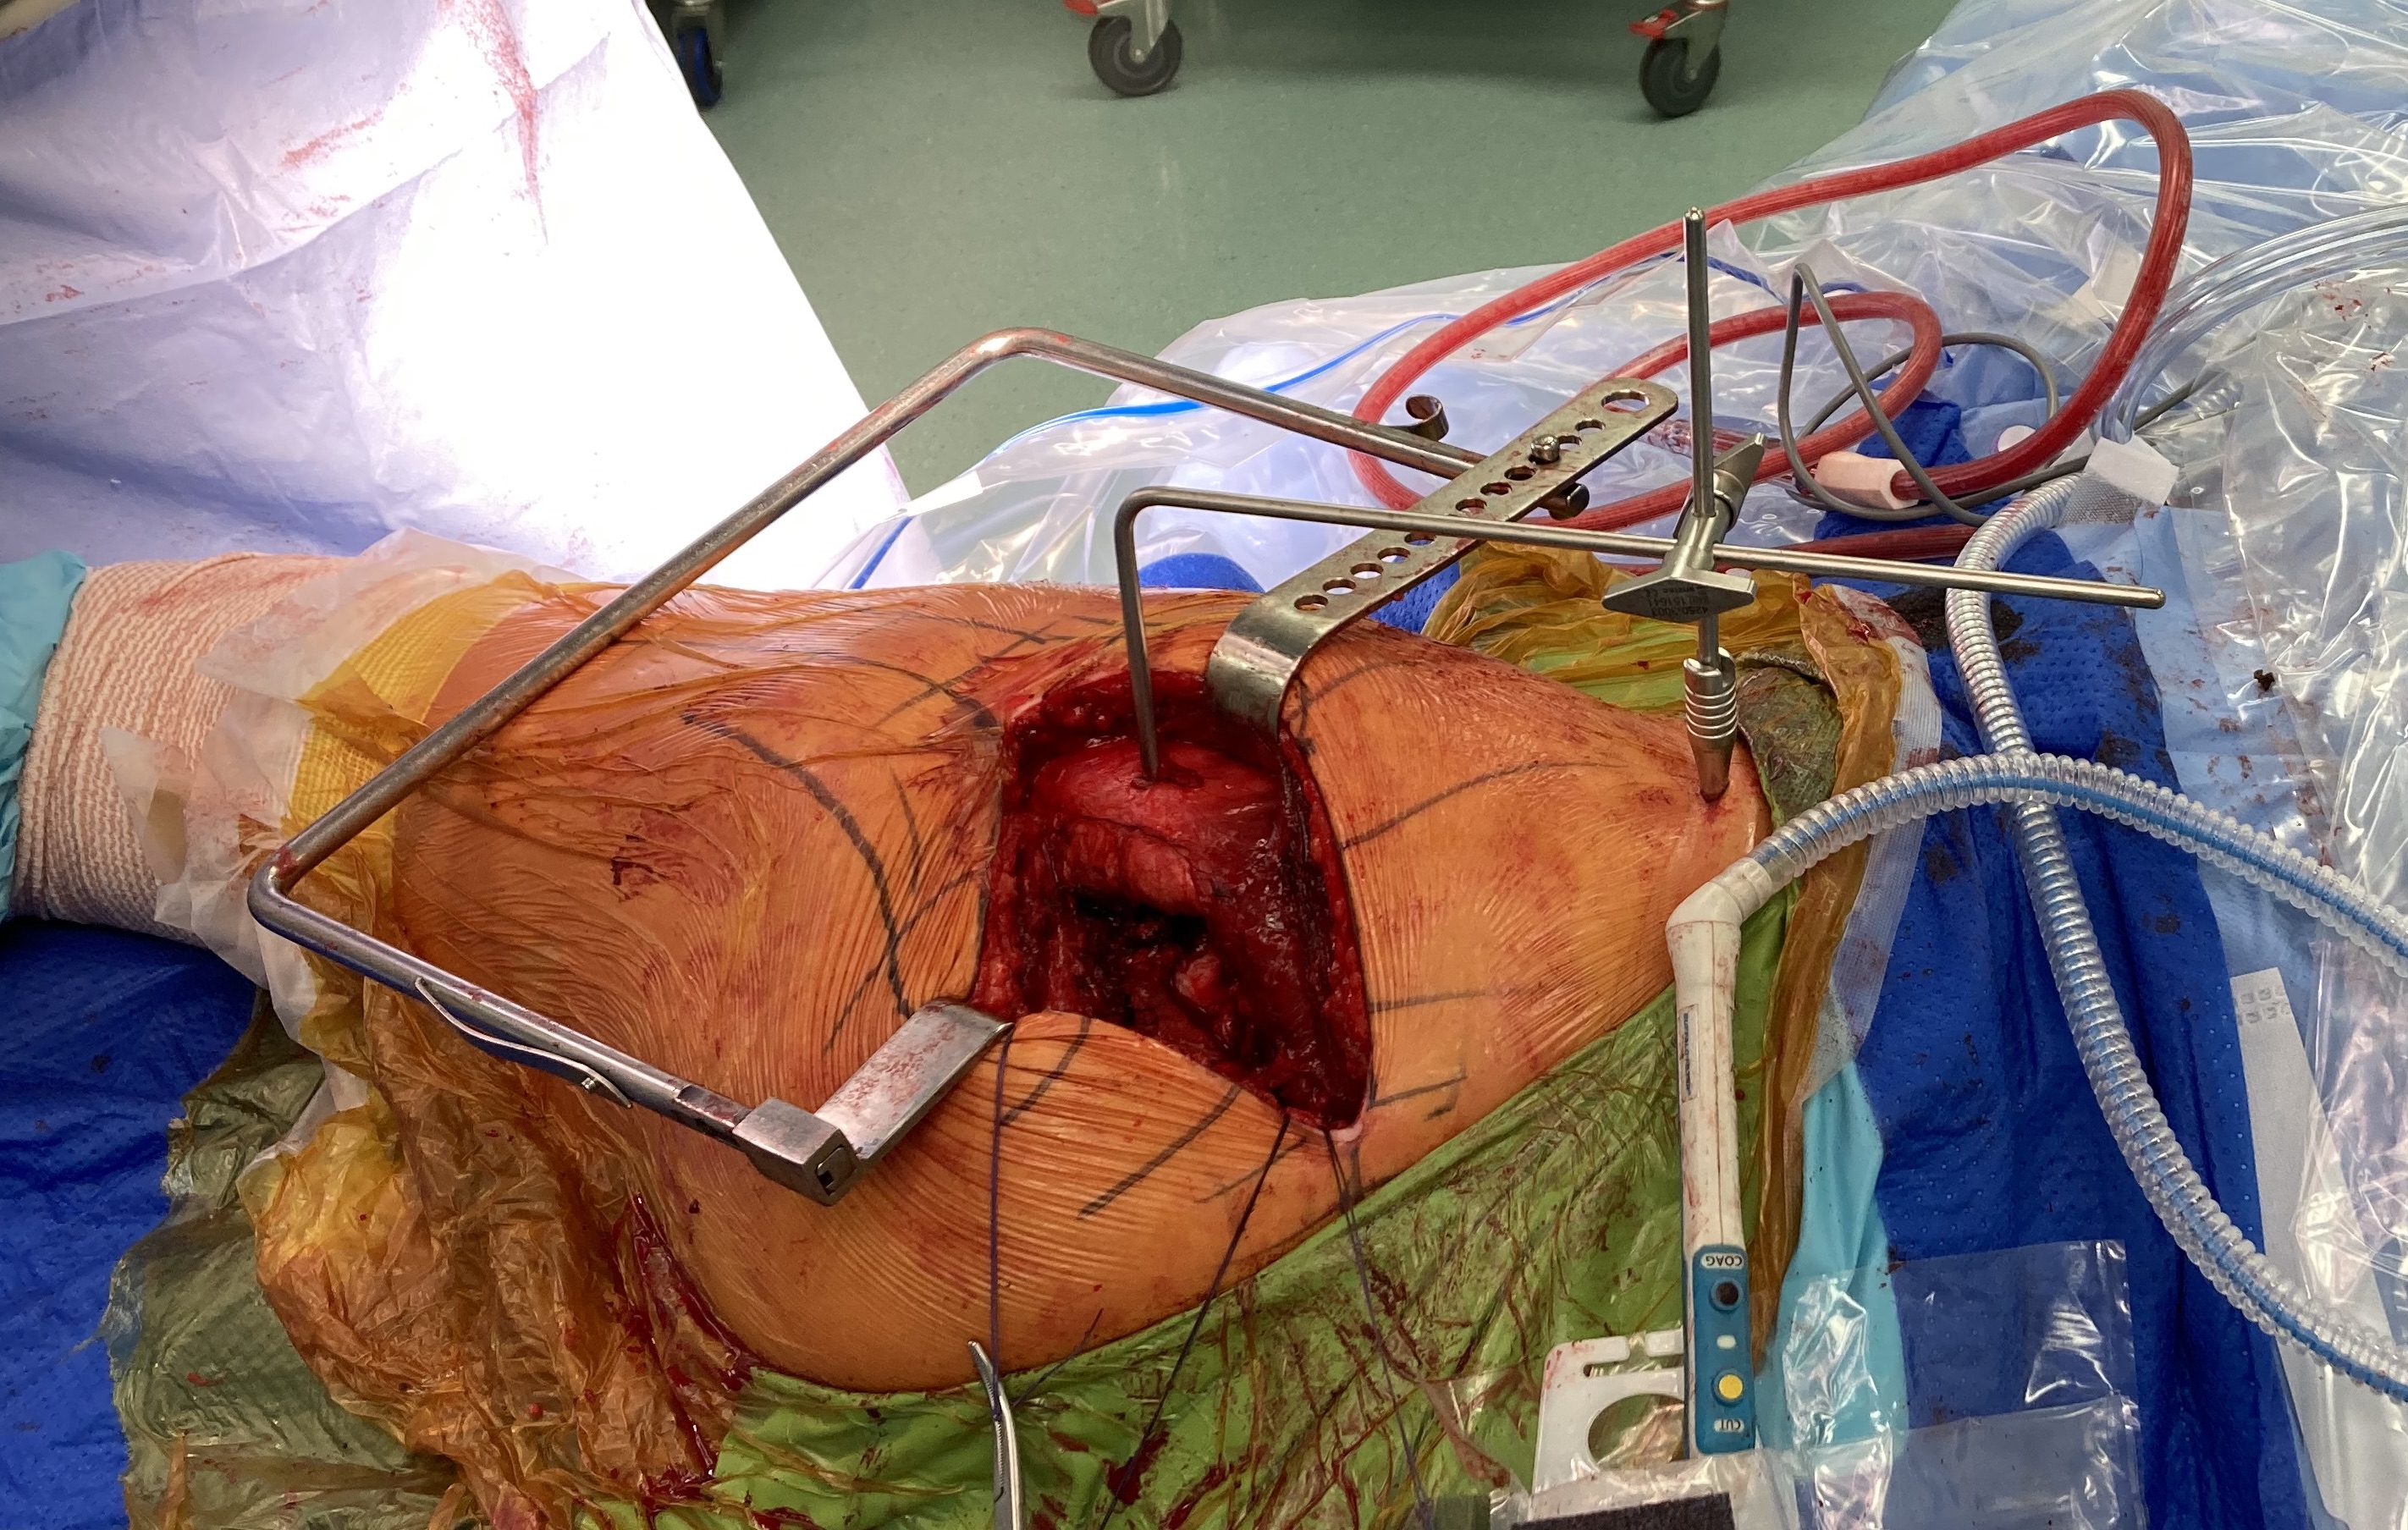

Mechanical referencing / Pins

Technique

- pin in pelvis / pin in femur

- must place leg in similar position each time to measure leg distance

- measure horizontal distance (LLD) and vertical distance (offset)

- comparison study of mechanical vs freehand

- mechanical reduces incidence of LLD